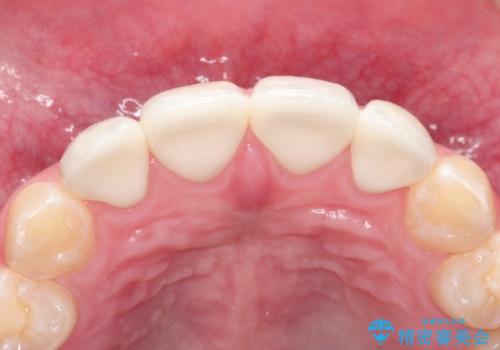

生まれつき歯の色が白濁しているところや、黄色くなっているところがあり、セラミッククラウンに審美的改善を行うこととしました。

ご自身の歯を削る必要がありましたが、セラミッククラウンを装着することで、審美的改善ができました。